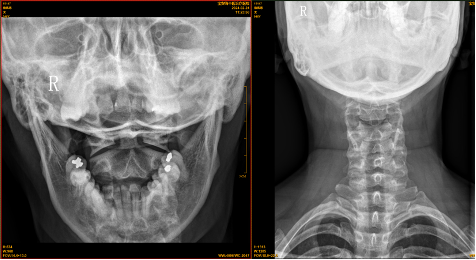

【影像】 颈椎X线片见颈椎平直,向右侧弯,C5-6椎间隙狭窄,椎体后缘骨质增生。C5-6、C6-7右侧椎间孔狭窄。右侧寰枢外侧关节对合不全,左侧显示不清,枢椎棘突偏左。

【讨论】本案症见右上臂酸痛无力、时有手指麻木,查体项僵、右椎间孔挤压试验(+)、颈椎右旋右上肢麻木,X线见颈椎平直、向右侧弯、C5-7右侧椎间孔狭窄,诊断为颈椎病。针灸治疗后症状减轻,貌似诊疗无误,实则不然。

患者右上臂酸痛无力、劳累右侧肩部酸痛、右侧卧位右上肢麻木可用颈椎病解释,与X线所见不冲突。而右手尺侧三指麻木为C7、C8神经根受压所致,X线仅见C5-6、C6-7右侧椎间孔狭窄,无法解释C8神经根受压。

右侧风池穴压痛(+)、右侧头后大直肌紧张压痛(+),X线片见右侧寰枢外侧关节对合不全、左侧显示不清、枢椎棘突偏左,考虑“寰枢关节紊乱”。患者没有颈枕部疼痛、旋转受限、头晕、头痛、失眠等相应症状,不能下 “寰枢关节紊乱综合征” 的临床诊断。